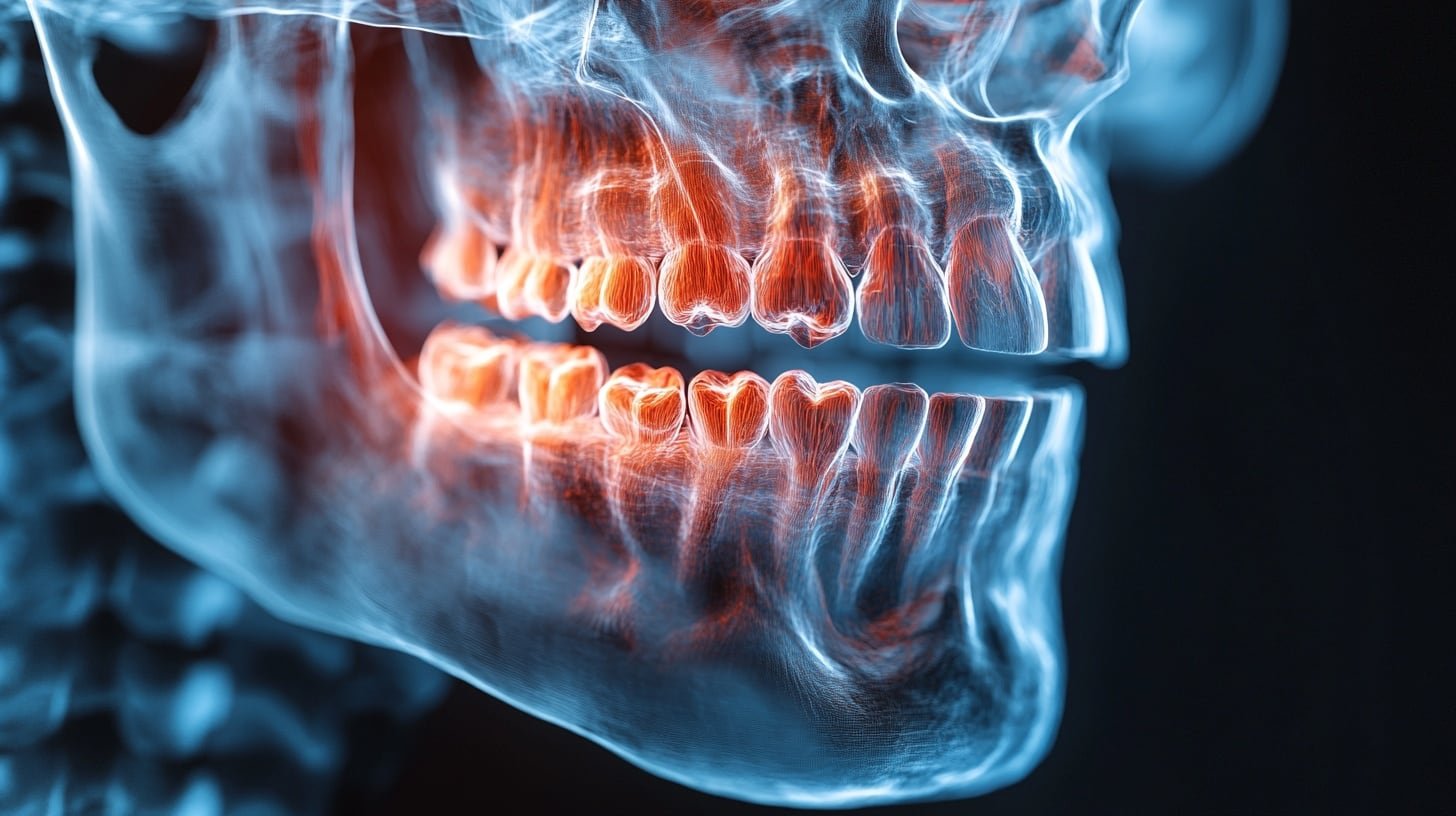

El dolor de mandíbula se ha transformado en una consulta recurrente en las clínicas dentales, vinculándose estrechamente con los periodos de estrés sostenido y las altas demandas de la vida moderna. Esta afección no es un inconveniente menor, ya que sus manifestaciones pueden derivar en cefaleas matutinas, molestias en los oídos, tensión facial persistente, chasquidos en las articulaciones y un desgaste severo del esmalte dental.

Una de las reacciones automáticas más comunes del cuerpo humano ante la ansiedad es el acto de apretar o rechinar las piezas dentales. Esta conducta, conocida técnicamente, suele ocurrir de forma inconsciente tanto en las horas de vigilia como durante el sueño profundo.

Dicha presión ininterrumpida sobre la musculatura mandibular altera su dinámica natural, provocando cuadros de dolor crónico. El primer paso para mitigar este impacto es aprender a reconocer el hábito y entender su conexión directa con el sistema nervioso.

La especialista en odontología estética, Jenni Rawes, señala que el factor psicológico desencadena una activación muscular involuntaria que repercute directamente en la zona maxilar. El efecto inmediato es una contracción de larga duración que se traduce en rigidez, sensibilidad extrema y dolor localizado. Entre los síntomas frecuentes, los pacientes reportan sonidos similares a un clic al gesticular, sensación de opresión en el rostro y dolores de cabeza intensos al despertar.

Cuando las medidas básicas no surten efecto, es imprescindible acudir a una evaluación profesional, especialmente si se confirma un cuadro de bruxismo. Esta condición se define por el hábito de apretar o rechinar los dientes sin que el individuo lo note, generando una sobrecarga extenuante en la articulación temporomandibular.